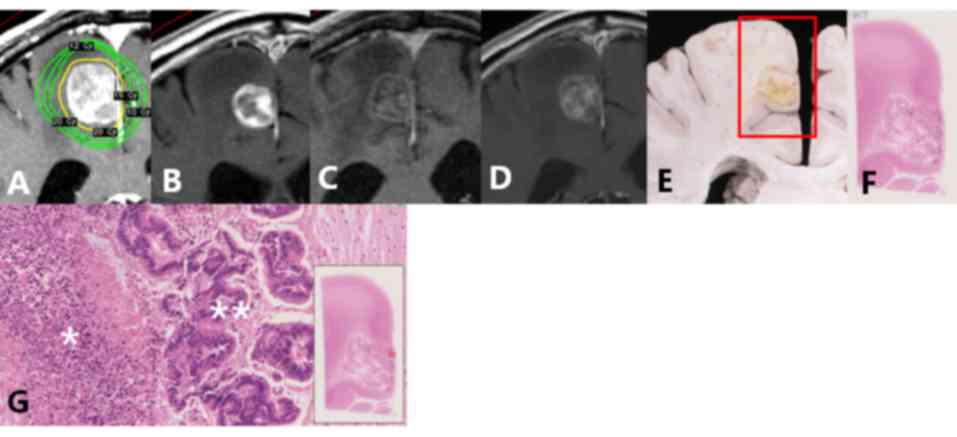

Table II summarizes the associations between the details of the last MRI and pathological results. A case of pathological failure is presented in Fig. 1 (lesion no. 1a). The contrast-enhanced areas on Gd-MRI contained various pathological components, including viable tumor cells, tumor necrosis, hemorrhage, inflammation and vessels. The degree of contrast on Gd-MRI was similar in all components. All viable tumor tissue and hemorrhages demonstrated contrast enhancement. Some areas of tumor necrosis, inflammation and vessels exhibited contrast enhancement, while others did not.

Figure 1.

Images and pathological findings of one case (lesion no. 1a). (A) Dose distribution at GKR. (B) Gd-MRI 1 month following GKR. (C) Gd-MRI 3 months after GKR, classified as SD in acute phase. (D) final Gd-MRI 7 months after GKR, classified as SD in late phase. (E) Macroscopic view at autopsy 10 months after GKR. (F) Histological examination. (G) *Tumor necrosis and **viable tumor cells were observed at the periphery and center of the lesion, respectively (magnification, 20×10). GKR, Gamma Knife radiosurgery; Gd-MRI, gadolinium-enhanced magnetic resonance imaging; SD, stable disease.